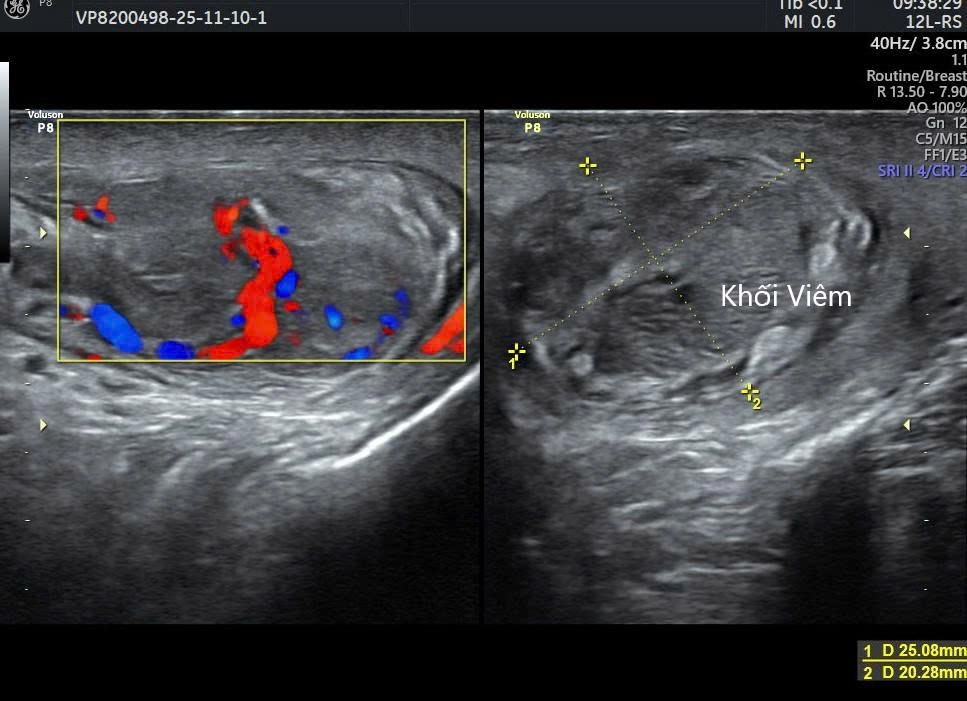

Điều trị cho bệnh nhân bị lậu mãn biến chứng viêm mào tinh hoàn. Nguyên nhân do điều trị lậu bằng thuốc nam 2 tháng